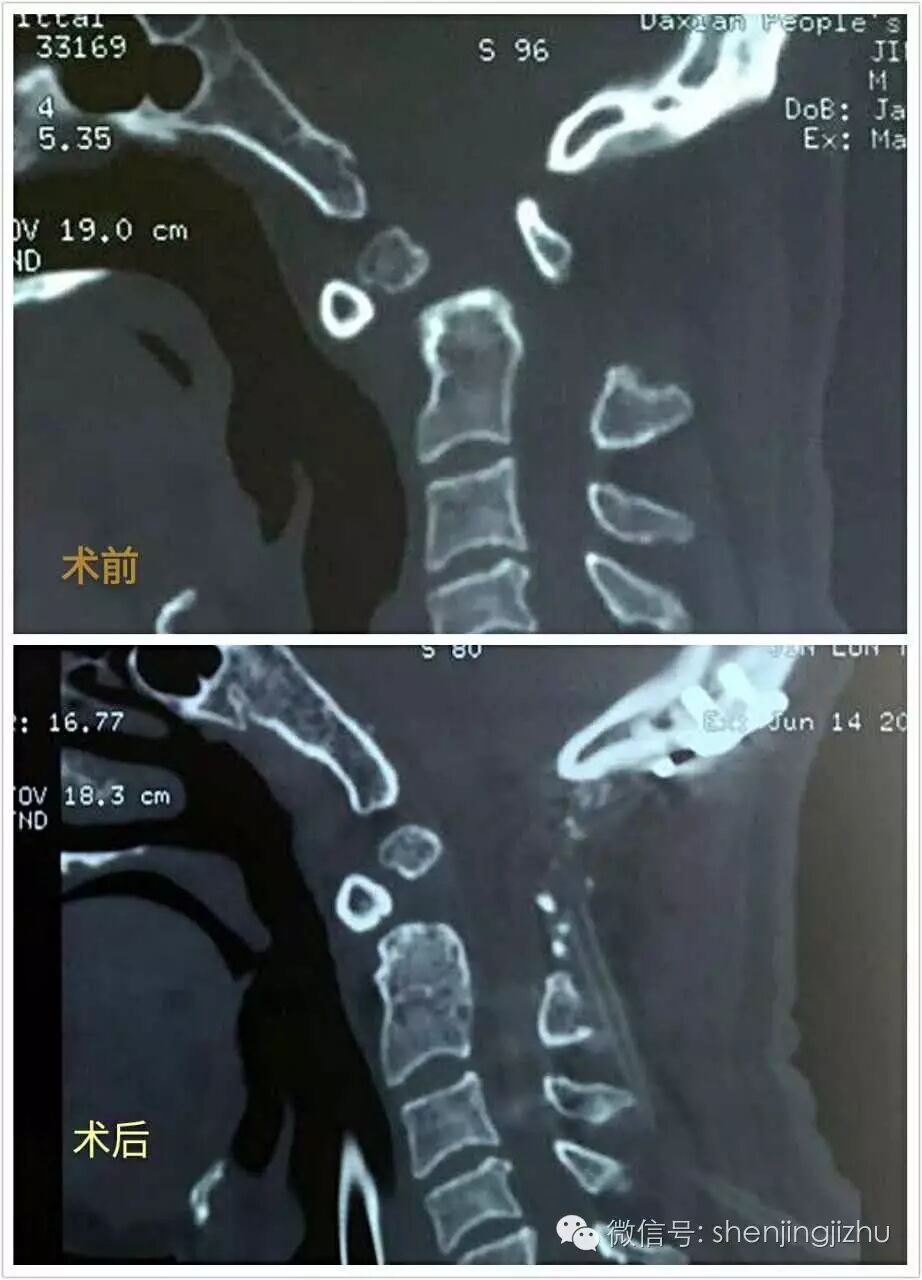

术后影像:

影像资料对比

手术方式可选择后路复位,枕颈融合或C1-2融合;

本例复位完美,延颈髓受压解除充分,术后患者症状明显改善。